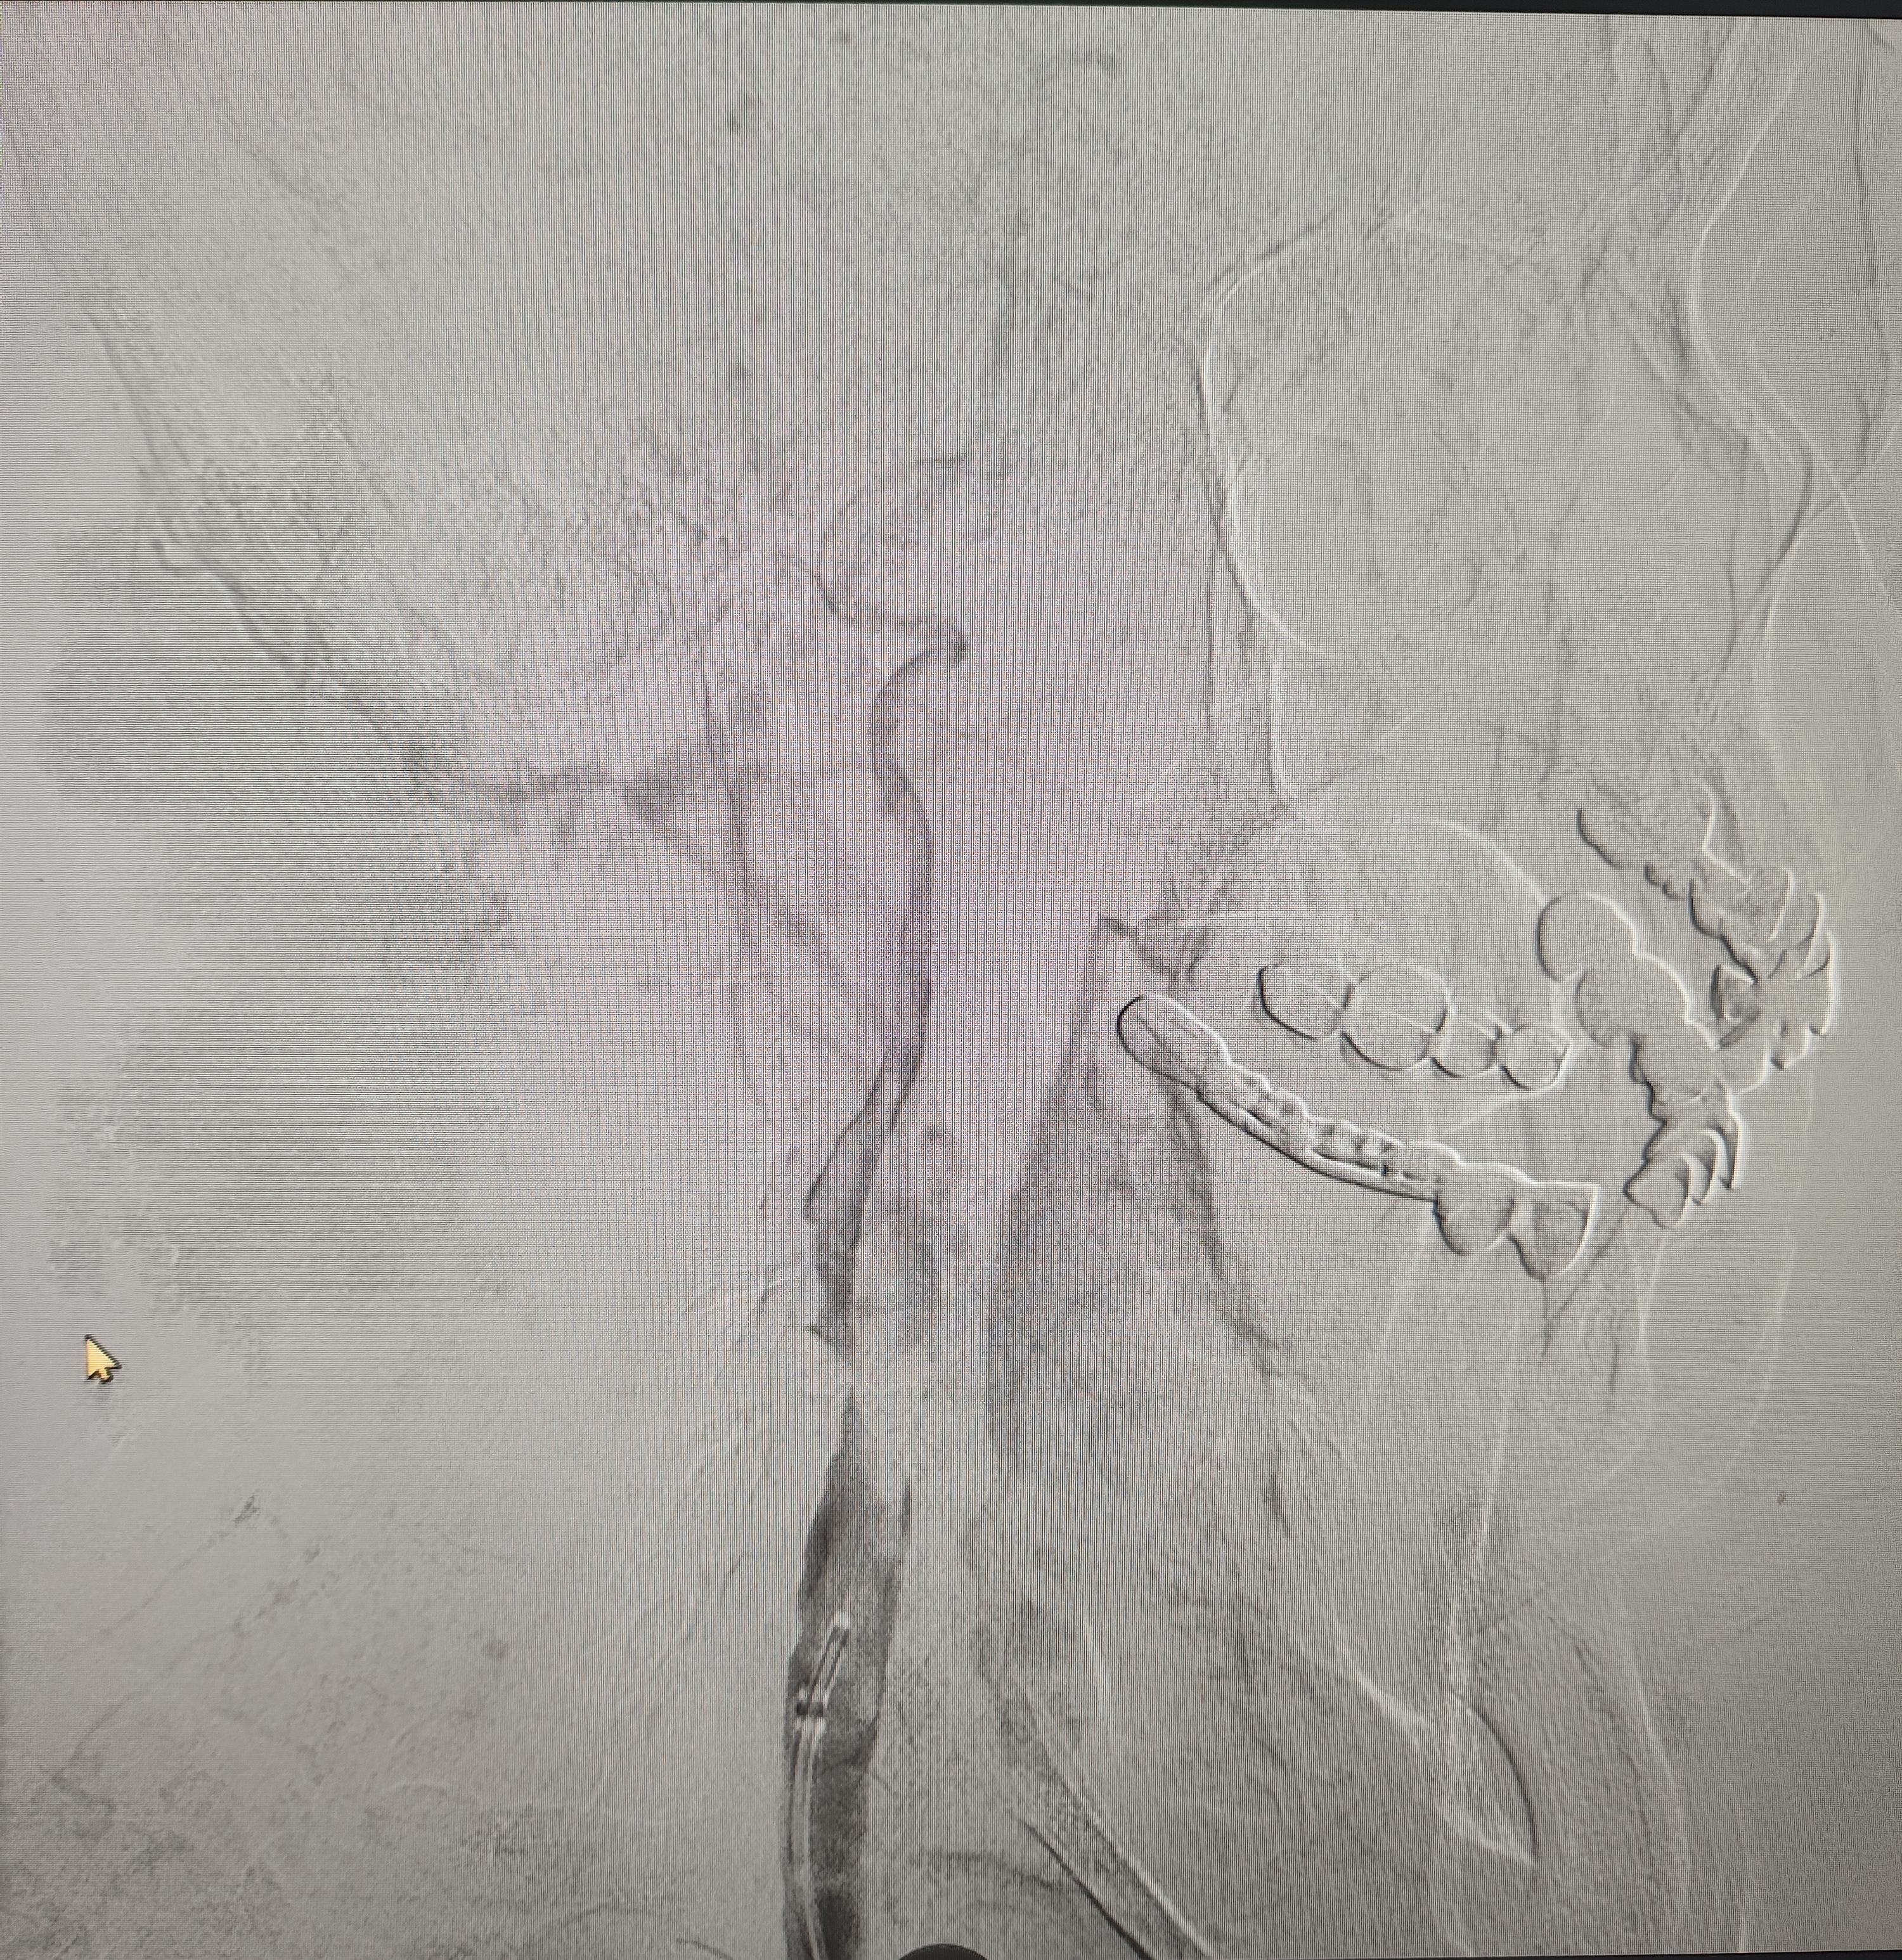

颈总巨大斑块急性闭塞的血管内治疗(双颈动脉支架桥接+支架释放后掉斑块,抽吸取栓)

急诊上台。